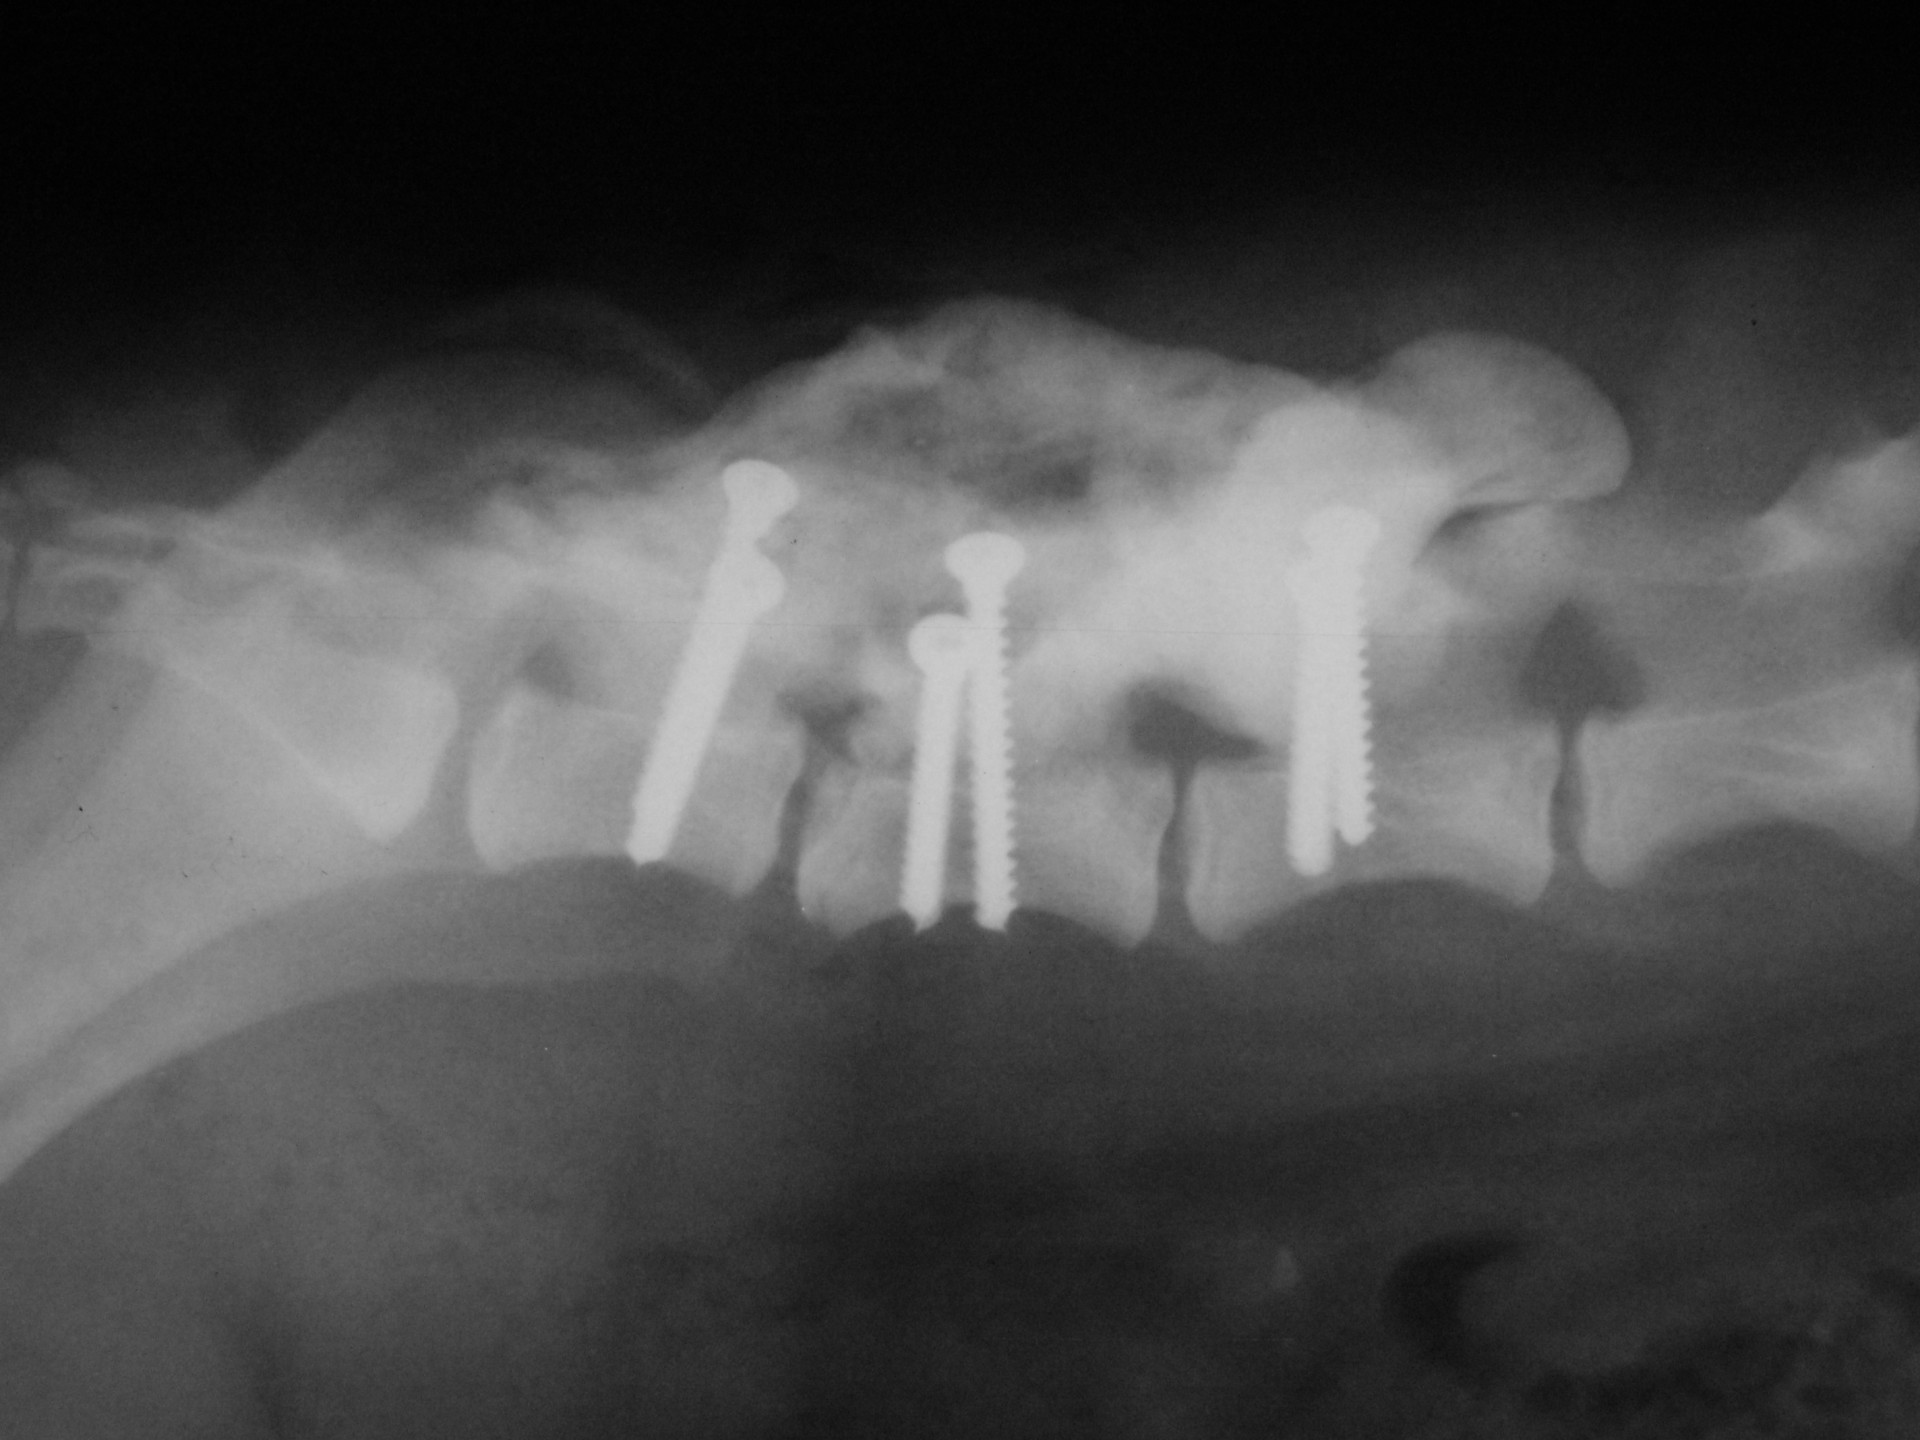

A gerinctörések műtéti ellátása kettős feladatot jelent: egyrészről a törés és elmozdulás következtében kialakult gerincvelő összenyomatást kell megszüntetni, másrészről a tört végeket kell adaptálni és eredeti állapotban - a további elmozdulás megakadályozása érdekében - rögzíteni. A műtéti ellátás során ezért minden esetben az érintett területen a gerinccsatorna felső csontos ívét eltávolítjuk (total laminectomia) így a gerincvelő sérülésének mértéke egyértelműen látható ill. a későbbi összenyomatása elkerülhető.

A törött csigolyatestek adaptációja és rögzítése a nyitott gerinccsatorna mellett komoly kihívást jelent. A későbbi elmozdulás elkerülésére többféle műtéttechnika alkalmazható, melyek közül a csigolyatestek lemezes osteosynthesise ill a fixateur interna használata terjedt el leginkább. Első esetben a sérülés előtti és mögötti csigolyákat lemez és csavarok segítségével egymáshoz rögzítjük, míg az utóbbi esetben a törés előtti és mögötti egy vagy több csigolyatestet két oldalról behelyezett csavarok és egy steril kétkomponensű akrilát műgyanta segítségével rögzítjük.

Szerencsés esetben az állat a műtétet követően néhány héten belül, akár tünetmentesen gyógyul. Az implantátumok későbbi eltávolítására - amennyiben szövődmény nem alakul ki - általában nincs szükség.

Bármilyen műtét után kialakulhat olyan szövődmény, mely gennykeltő baktériumok műtéti sebben történő elszaporodásával jár (szeptikus szövődmény). Különösen igaz ez olyan beavatkozásokra, amikor valamilyen idegen anyag (implantatum) kerül a szervezetbe beültetésre. Ilyen idegen anyag a gerinctörés műtéteknél használatos fixateur interna rögzítőanyaga (akrilát műgyanta) is. Abban az esetben, amikor a szeptikus szövődmény antibiotikumok célzott adásával nem gyógyítható, a test számára idegen anyagot el kell távolítanunk. A gerinctörés műtéténél ez a nyitott gerinccsatorna miatt fokozott kockázatot jelent. Az implantatum eltávolítását követően azonban a szeptikus folyamat gyógyul és a helyén kialakuló kötőszövet a fixateur externának megfelelően rögzíti a gyógyulófélben lévő csigolyát is.